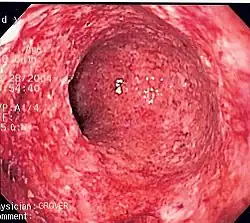

Morphologic patterns

Specific patterns of acute and chronic inflammation are seen during particular situations that arise in the body, such as when inflammation occurs on an epithelial surface, or pyogenic bacteria are involved.

- Ulcerative inflammation: Inflammation occurring near an epithelium can result in the necrotic loss of tissue from the surface, exposing lower layers. The subsequent excavation in the epithelium is known as an ulcer.